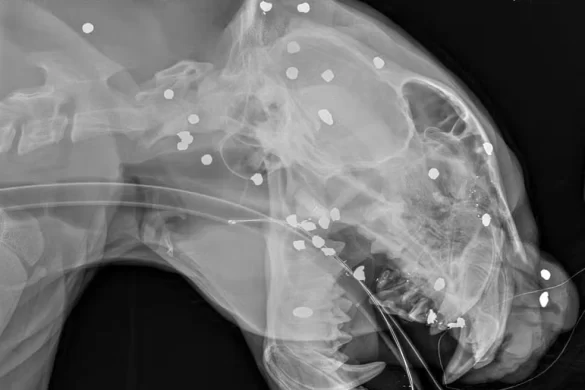

Raio-X revela mais de 30 estilhaços de tiro em onça resgatada no Rio Negro, em Manaus

Uma onça-pintada resgatada após ser encontrada à deriva nas águas do Rio Negro, em Manaus, foi submetida a exames de raio-X que mostraram mais de 30 estilhaços de tiro espalhados pelo rosto, cabeça e pescoço. A informação foi confirmada nesta quinta-feira (2) pela equipe de veterinários responsável pelo atendimento.

O animal, um macho com cerca de cinco anos, apresentava ainda dentes quebrados, ferimentos visíveis na cabeça e sinais de intensa debilidade. Segundo especialistas, o disparo, possivelmente feito com arma de caça a longa distância, espalhou os estilhaços pelo corpo. “Se tivesse sido um tiro concentrado, o animal teria morrido na hora. Pela dispersão, acreditamos que tenha sido uma tentativa de afugentamento”, explicou o biólogo e pesquisador de felinos Rogério Fonseca.